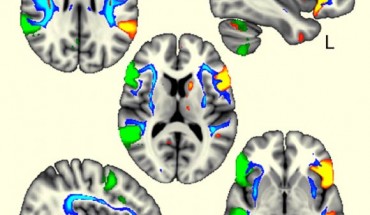

A team of researchers from the University of Oxford has identified four regions of the human genome associated with left-handedness in the general population and linked their effects with brain architecture. The language brain regions were more coordinated in left-handers between the two sides of the brain (in green and orange) and were also connected by the white matter tracts influenced by one genetic region related to handedness (in blue). Image...